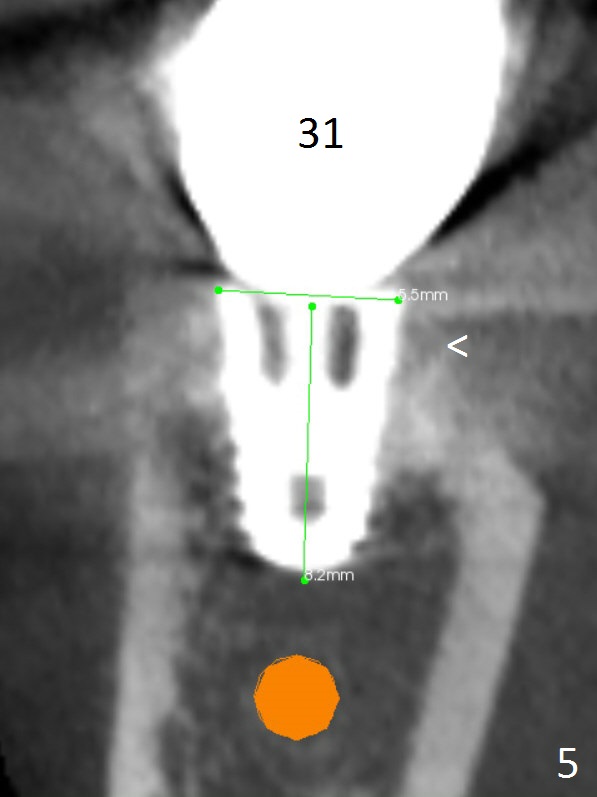

The mesial (Fig.1 >) and lingual (Fig.5 <) threads of the implant at #31 appear to be further bone graft to prevent periimplantitis.